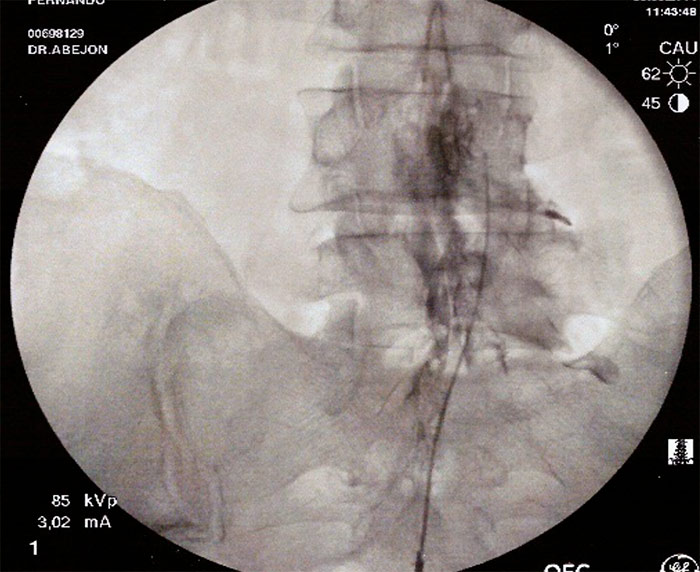

Con el paciente en decúbito prono, se coloca una almohada a la altura de la pelvis para corregir la lordosis fisiológica, y el arco de fluoroscopia en posición AP , con el  marcador radiopaco se localiza la línea media, se gira el arco de fluoroscopia a posición lateral para localizar el hiato sacro. Una vez localizado se infiltra con anestesia local de la piel, tejido celular subcutáneo, ligamento sacrocoxigeo y periostio, y se realiza punción con una aguja introductora con visión continúa hasta atravesar el ligamento sacrocoxigeo, se  administra contraste radiopaco (2-5ml) en visión continua y se comprueba su distribución. Posteriormente se vuelve a comprobar la distribución del contraste con el arco de fluoroscopia en posición anteroposterior (epidurografía). La epidurografía nos permitirá identificar las raíces que no se rellenan con contraste (fibrosis).

A continuación se introduce un catéter y se dirige hacia la zona de amputación radiológica, en el espacio epidural anterior. Con el arco de rayos en posición lateral, se inyectan 10ml de suero salino 0.9% con 1500v de hialuronidasa en la zona de amputación, posteriormente se inyecta de 3-5ml de contraste radiológico para visualizar la apertura del espacio, y a continuación se inyecta 9ml de Bupivacaina 0.25% y 40mg de triamcinolona. Se retira la aguja introductora y el catéter y se coloca un apósito. Hay autores que dejan el catéter durante 3 días y vuelven a inyectar el anestésico local y suero salino fisiológico al 10% (está en discusión). Con el catéter de RCE Cosman, se dirige a la zona amputada de contraste, se sigue el procedimiento anterior y además se intenta dirigir la punta del catéter debajo del pedículo que es donde se encontraría el ganglio de la raíz dorsal y se procede a hacer radiofrecuencia pulsada (estimulo sensitivo alrededor de 0.5v y el 45v, por un periodo de 2 a 8 minutos.